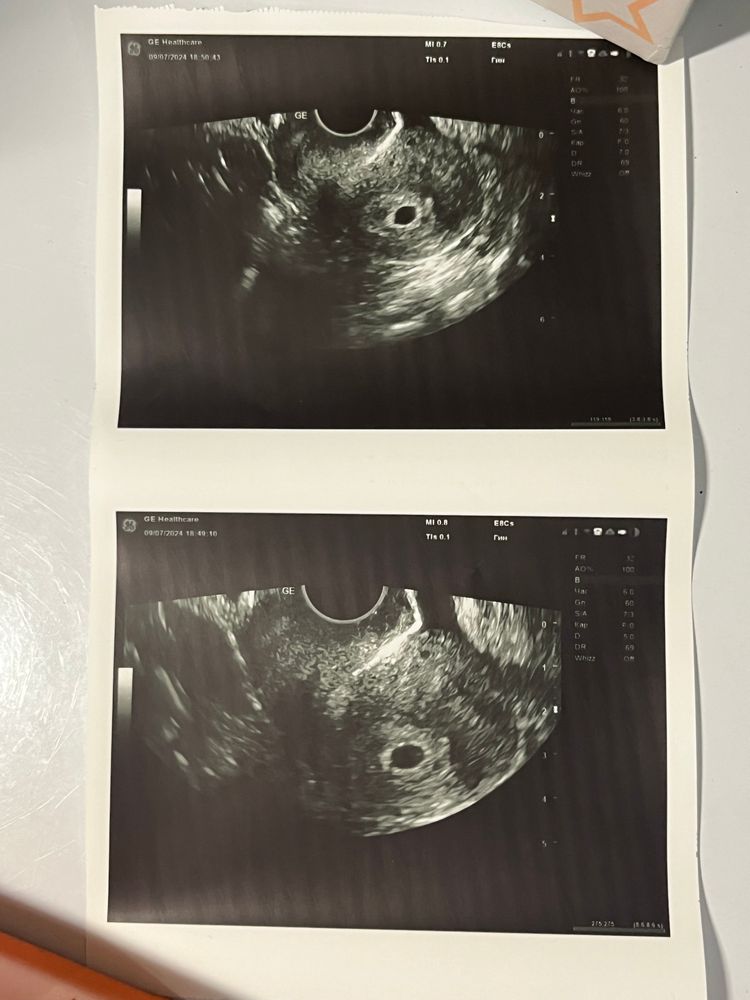

Первое УЗИ на 5,5 недель беременности

Вроде все нормально. Врач сказала, что срок соответствует 4,5 недель…что странно. Итого полный комплект: ХГЧ 4024, Прогестерон 4,83 (с сегодняшнего дня принимаю Утрожестан 200, через недельку +- на пересдачу) и вот УЗИ. Нашла его прям сразу же. Сказала, что он у меня сзади вроде, не совсем поняла, была так рада видеть его) Ретрофлексио в общем…но вроде это не критично и не мешает беременности. По крайней мере, после встречи с бусинкой я успокоилась)

Молодец, что оперативно сбегала на УЗИ, вроде всё хорошо) по срокам и размерам я пока не особо разбираюсь, но что беременность маточная, желточный мешочек есть и хорион - отличные поводы выдохнуть и порадоваться на этом этапе 😉

Очень странное узи) если срок поставила 4,5 то ктр никак не может быть 4 мм. На 4.5 неделях не видно эмбрион. Может имела ввиду эмбриональных?

Алина А, нет) я уточнила у нее верно ли она срок указала - 4,5 акушерских недель, на что она подтвердила. Я тоже удивлена. Почитала в просторах интернета и здесь на сайте - размер ктр соответствует 5-6 неделям. По идее, даже моему сроку 5.5 недель это соответствует, она на неделю занизила мне)

Лина, мне просто мало понятно как в ПЯ 8/6 поместился ктр 4 мм и жм 3мм) там вообще тогда места нет)